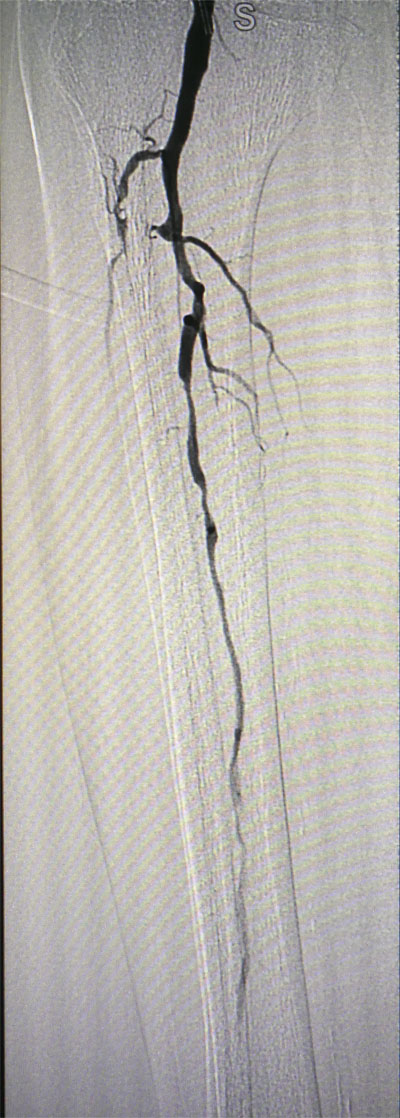

放射科導(dǎo)管室內(nèi)做好了術(shù)前準(zhǔn)備,患者由無創(chuàng)呼吸機(jī)及各種循環(huán)支持下開始介入手術(shù),術(shù)中重癥監(jiān)護(hù)科嚴(yán)密觀察患者的生命體征,內(nèi)分泌科醫(yī)生負(fù)責(zé)手術(shù),患者下肢血流極差,膝下僅存一條多處嚴(yán)重狹窄的腓動脈供血,主要供血的脛前動脈及脛后動脈均長段閉塞,順行穿刺成功后導(dǎo)絲下行困難,故采用踝下脛后動脈逆穿對接技術(shù)成功通過病變。經(jīng)過近5個小時的奮斗,手術(shù)順利完成,患者腓動脈及脛后動脈血流通暢,血流直達(dá)足底動脈環(huán),患者感到足部逐漸溫暖,術(shù)后清創(chuàng)時患者創(chuàng)面血流豐富。

治療前